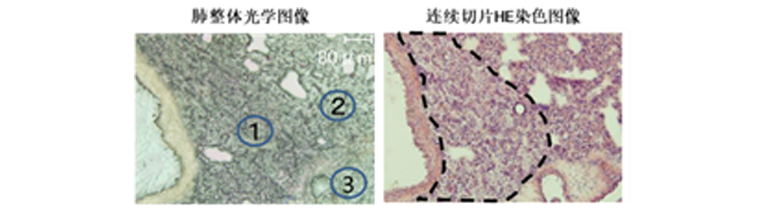

质谱成像中高灵敏度分析也是至关重要的,尤其在药物代谢研究中对低浓度代谢物分布的研究。iMScope QT在硬件性能上较之前作了较大提升,后端Q-TOF型LCMS-9030的接入提高了质谱检测的灵敏度。在本次开机测评中,小编分析了给药后的大鼠肺中抗心律失常药物胺碘酮及其代谢物的分析,明确了药理学研究中的发现是胺碘酮副作用引起。

给药后的大鼠肺部病理切片分析发现坏死区域

质谱成像发现抗心律失常药物胺碘酮及其代谢物在坏死区域的分布,明确了药理学研究中的发现是胺碘酮副作用引起。